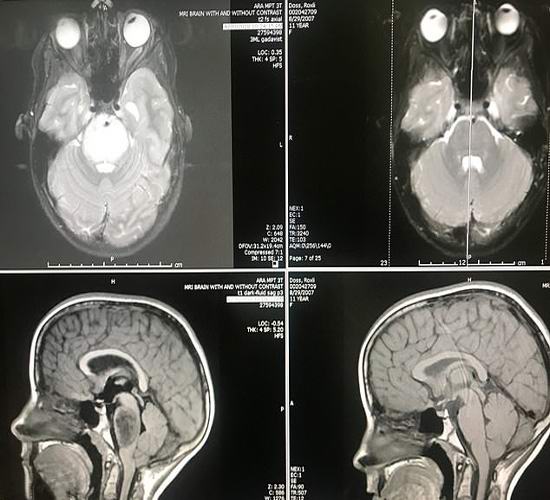

Az orvosok előrejelzése azonban mindenki meghökkentésére nem vált valóra. több emellett jelenleg mágneses rezonancia képalkotás is zajlik azt mutatja, hogy a daganat teljesen eltűnt Roxley agyában! Az orvosok nem ésszerű magyarázatot találhat arra, ami történt, mert tudományos bizonyítékok szerint ez egyszerűen nem lehetséges. Az orvosok felismerik amely még soha nem találkozott ilyen spontán és egy nagy rosszindulatú agydaganat gyors regressziója. az van egy igazi csoda.

Egy ritka, agresszív daganat, amelyet Doss-ban találnak évente 200-300 amerikainál fordul elő, ezen betegek mindegyikében ítéltnek tekintik. Ritkán él legalább kilenc ember hónappal a betegség kimutatása után. Így a hősnőnk, ítélve az egész egyedülálló beteg. Az orvosok gondosan szándékoznak vizsgálja meg a lány immunrendszerét annak meghatározása érdekében mindazonáltal az iskolás testének sikerült ellenállnia a halálosnak a betegség.